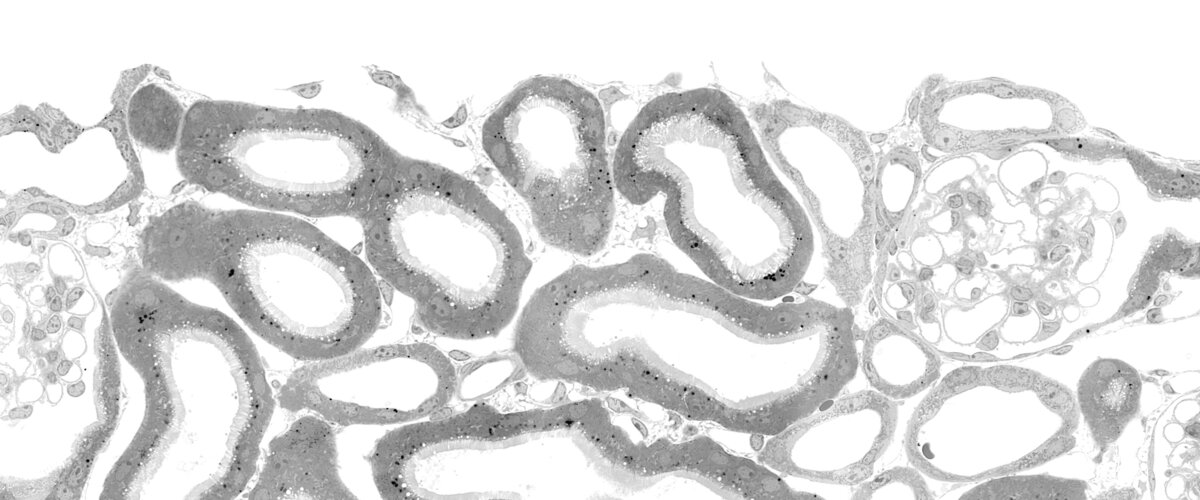

Die Erforschung der Funktion von Ionenkanal- und Membrantransportproteinen sowie die Aufklärung der Pathophysiologie monogenetischer Erkrankungen stehen im Mittelpunkt der wissenschaftlichen Arbeit unseres Lehrstuhls. Wir untersuchen diese Mechanismen vor allem in zwei Organen: der Nebennierenrinde und der Niere. Diese Verknüpfung von Grundlagenforschung und medizinischen Fragestellungen steht auch im Mittelpunkt der Lehre im Studiengang „Molekulare Medizin" (B. Sc.).